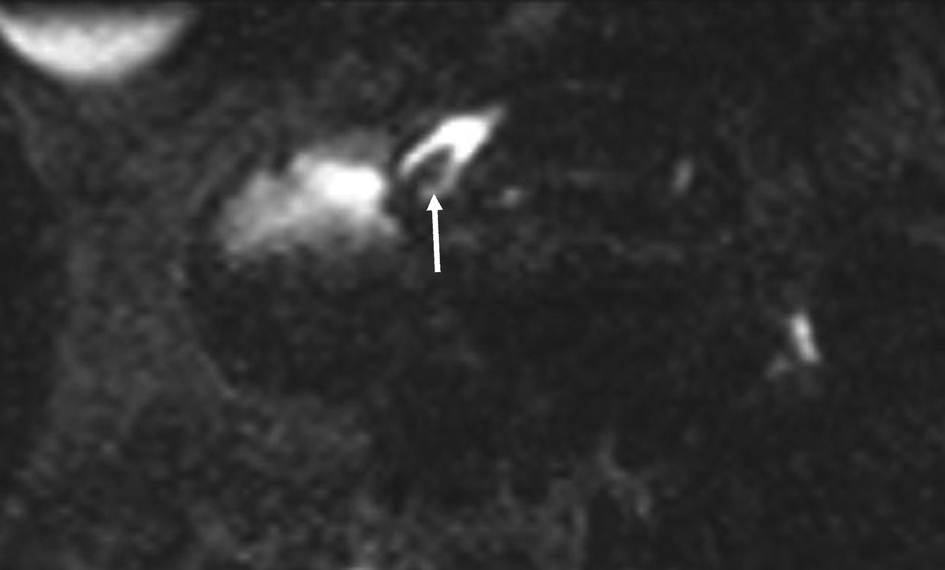

Figure 3. Pre endoscopic treatment; 3 mm axial MPR reformat through the minor papilla. The stone (arrow) is clearly visible in the ampulla of the accessory pancreatic duct.